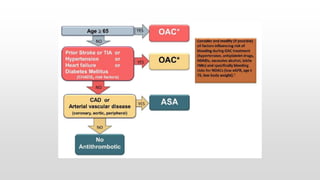

This document discusses various cases of collapse and syncope. It defines collapse as transient loss of consciousness with loss of postural tone and full recovery. Syncope is defined as loss of postural tone with or without loss of consciousness and full recovery. It then discusses the multiple potential causes of collapse and syncope including toxicological, cardiac conduction abnormalities, structural cardiac issues, autonomic dysfunction and more. It then goes through 9 case examples, discussing important questions to ask, potential tests and interventions for each case.